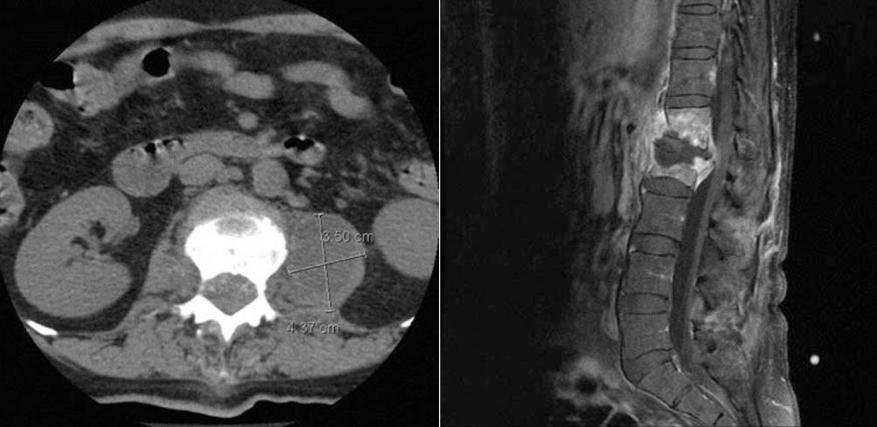

布鲁氏菌性脊柱炎伴腰大肌脓肿

左图 腰椎CT显示L1/L2终板破坏,伴严重椎管狭窄,左侧L1到L3腰大肌脓肿(3.50×4.37 cm)。

右图 腰椎MRI显示病变侵入椎管伴狭窄,T12可见呈高信号的椎体感染病灶。